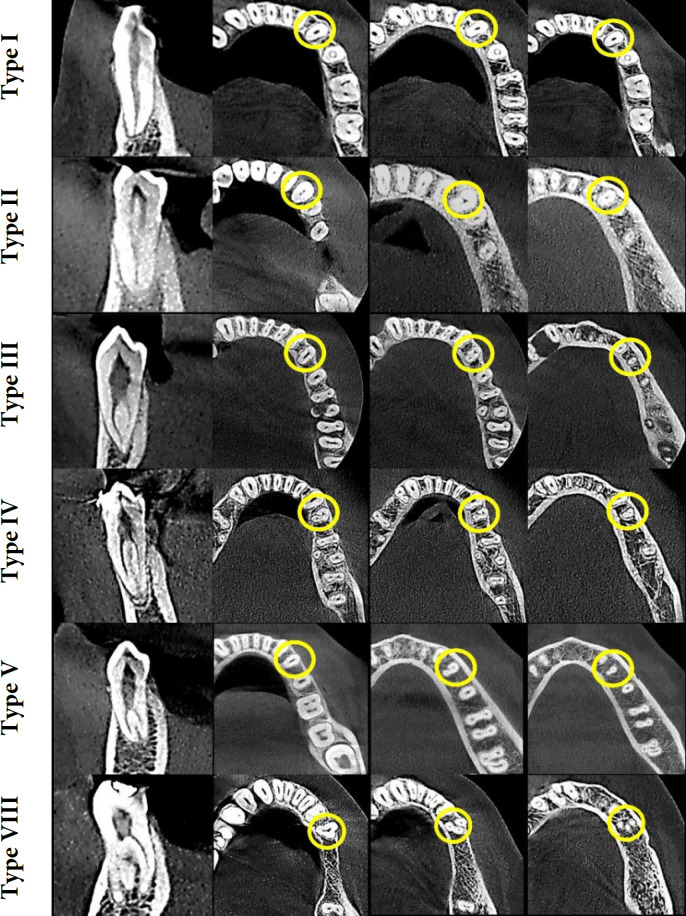

Result: Of the two hundred twelve teeth evaluated, 130 (61.3%) were first premolars, and 82 (38.6%) were second premolars. Most first premolars (78.5%) and almost all second premolars (97.6%) had one root. Morphological types of root canals were identified based on Vertucci's classification types I, II, III, IV, V, or VIII, and type I was the most frequent. There were no significant associations between number of roots and sex (P>0.05).